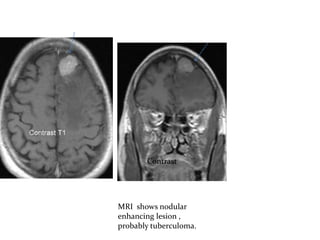

Contrast

MRI shows nodular

enhancing lesion ,

probably tuberculoma.

MRI shows nodular enhancing lesion ,